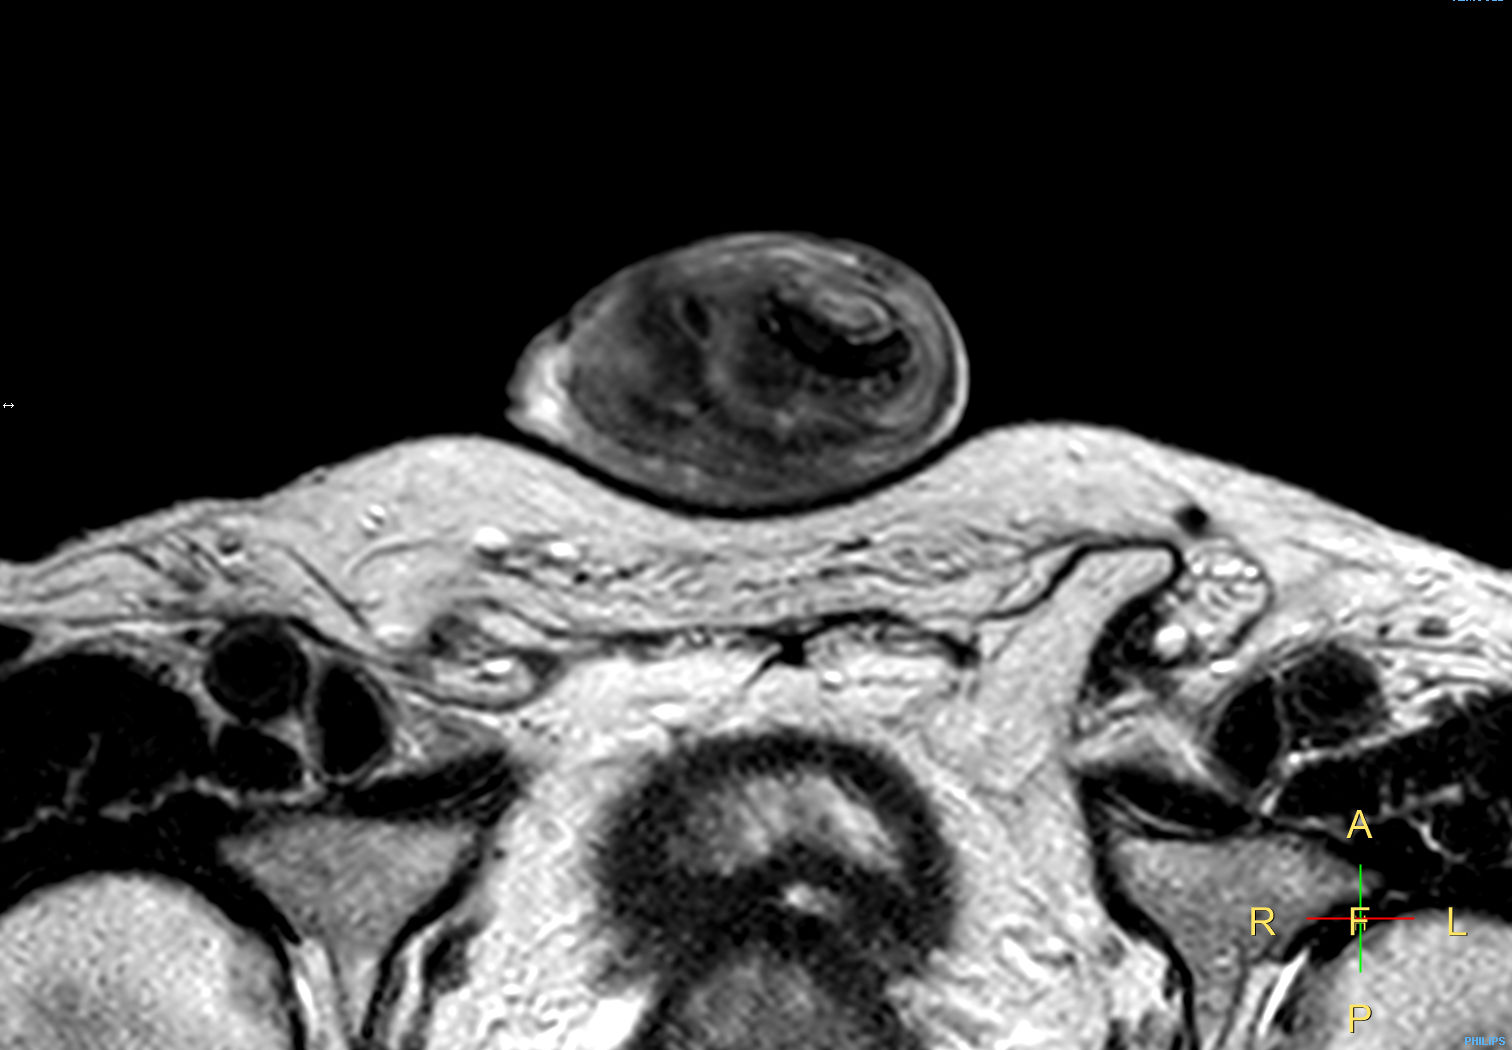

Patient with a penile carcinoma. ExamCard includes Compressed SENSE to shorten exam time, diffusion to achieve high contrast between background and lesions, and MultiVane XD for motion-free imaging in short scan time.

T2w TSE FatSat Compressed SENSE